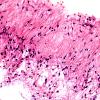

DEVELOPMENTAL MALFORMATIONS

Cyst - Arachnoid (4)